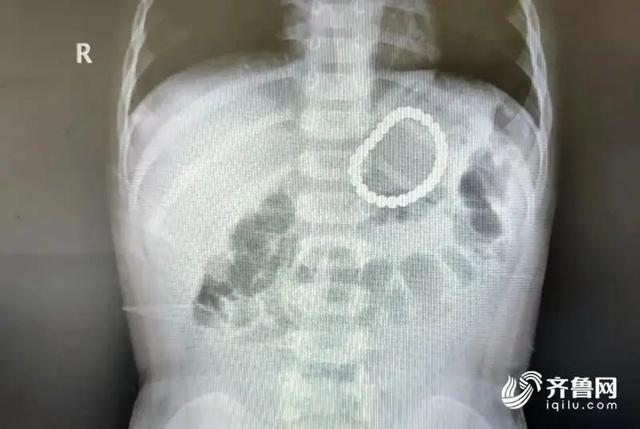

果不其然,在X光下,

幼童的左上腹部出现一个串珠样的异物。